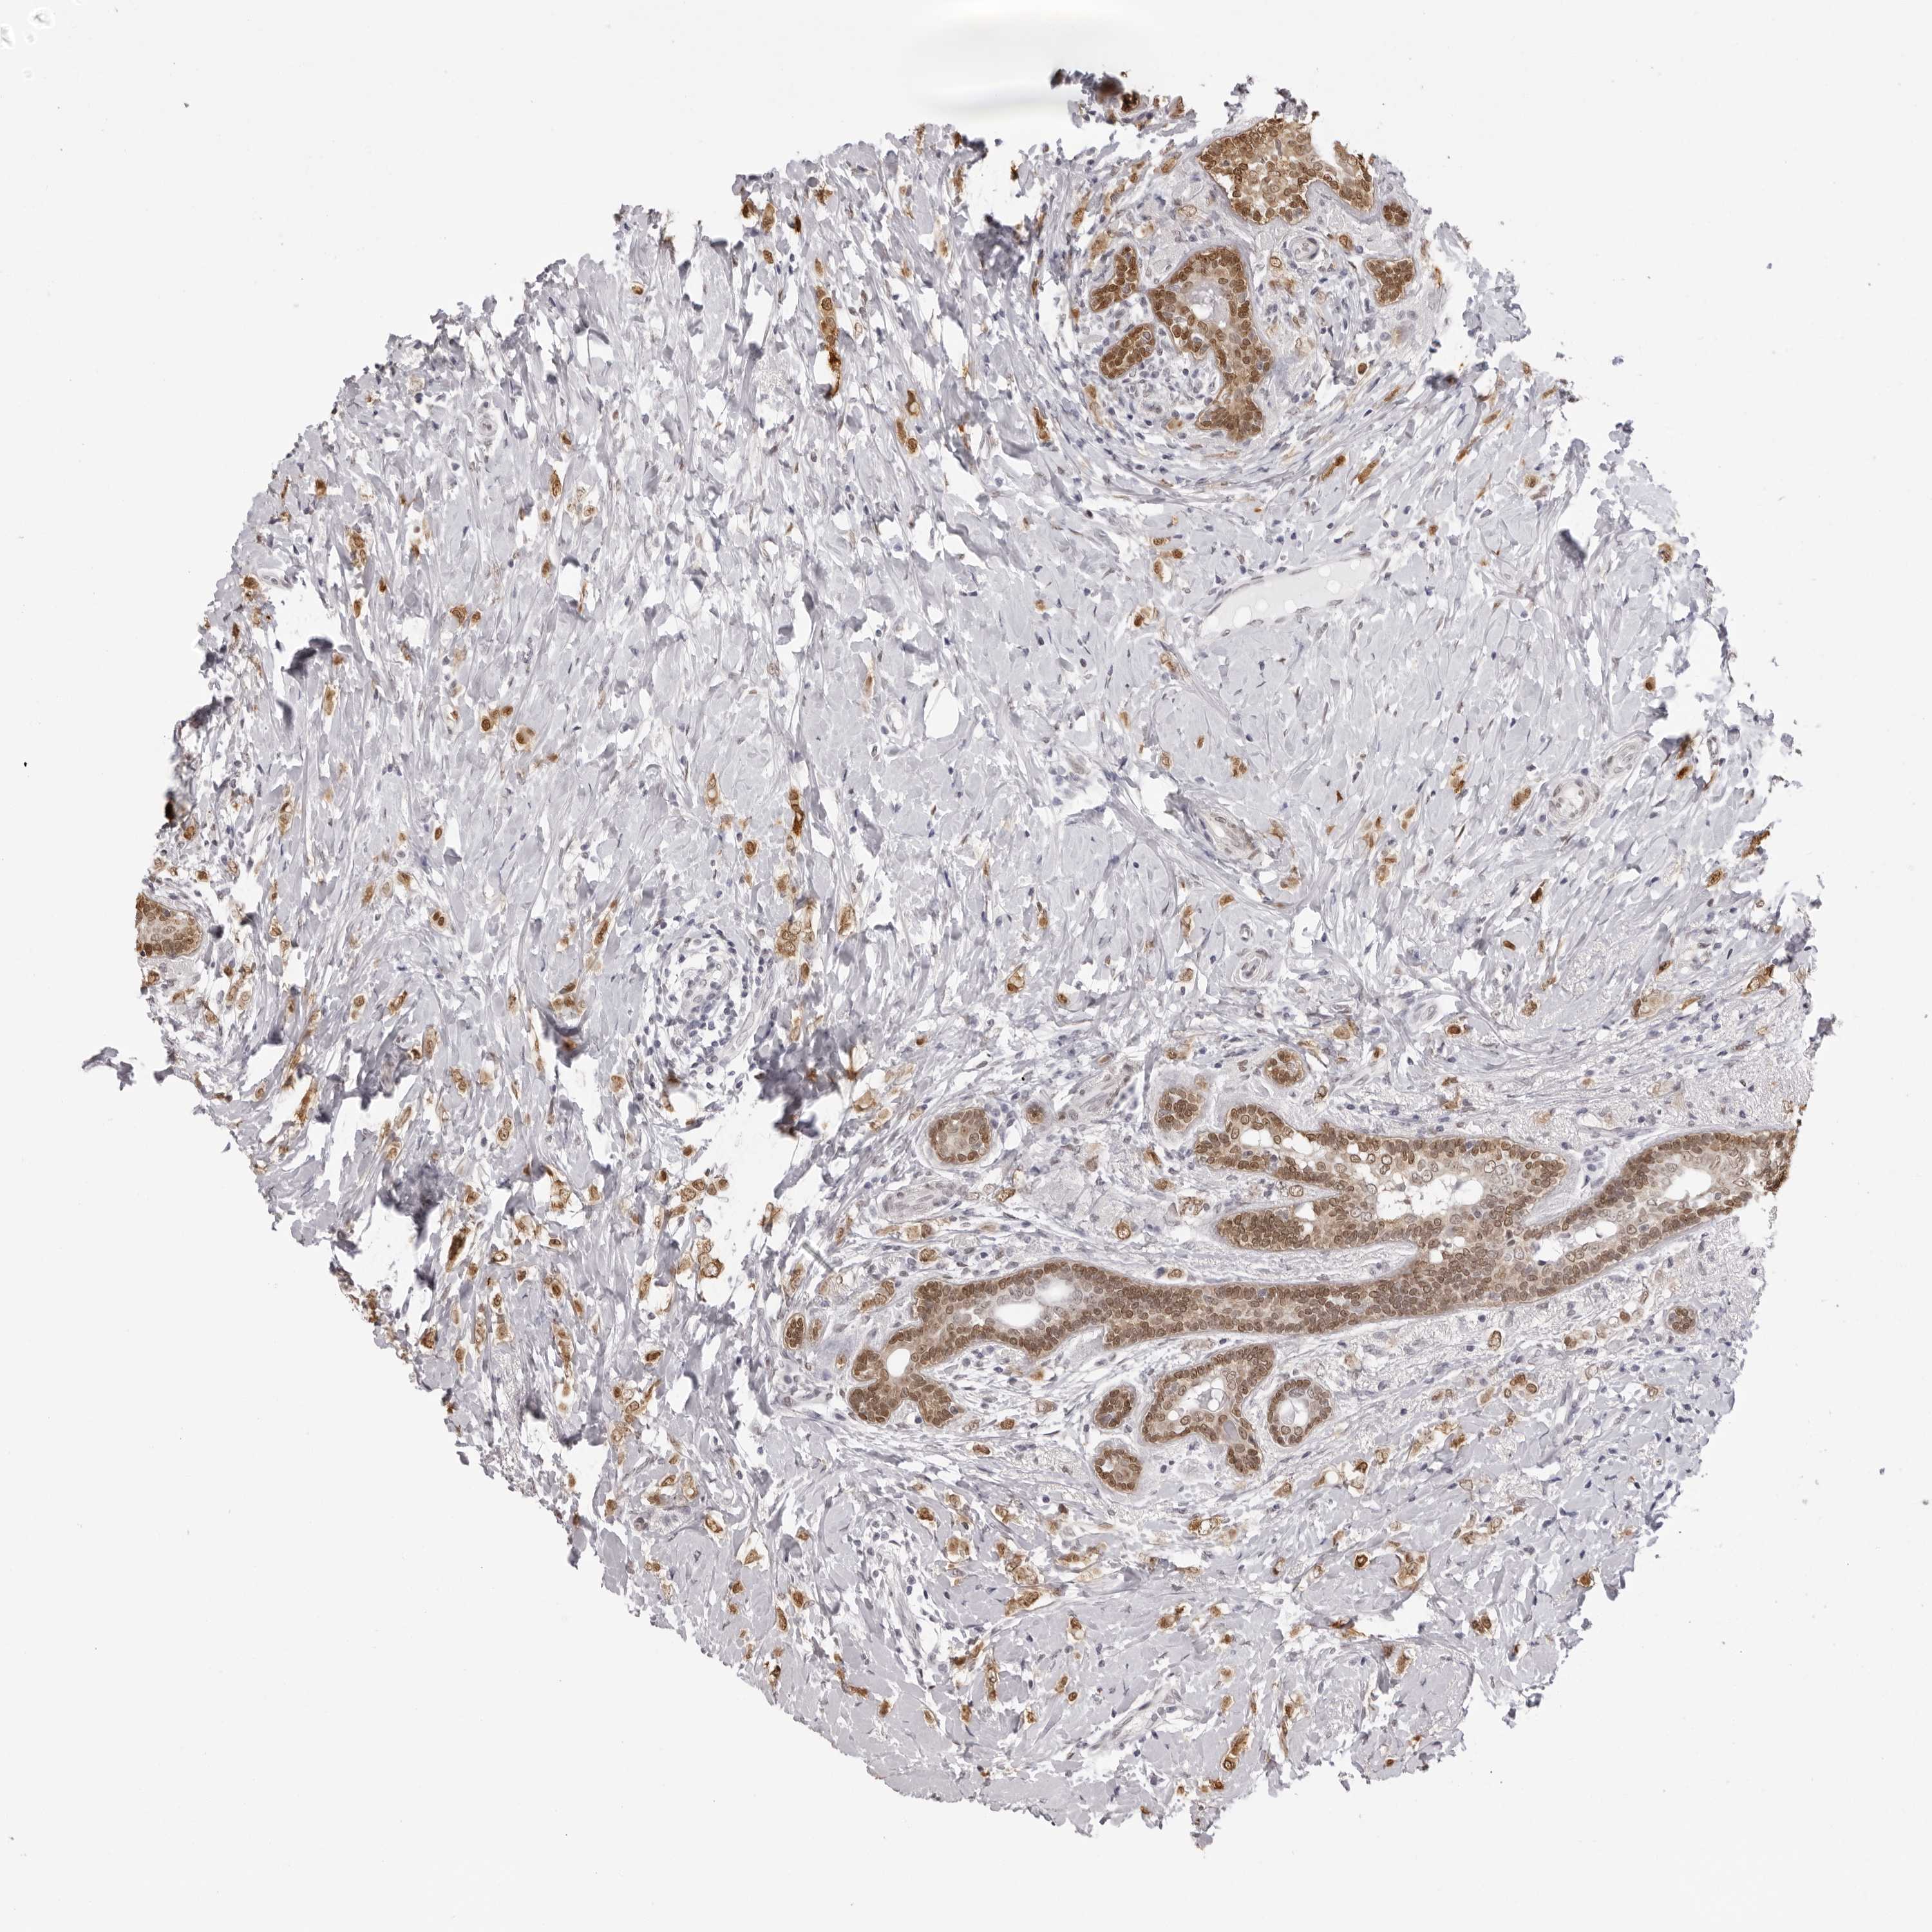

CANCER BREAST CANCER Show tissue menu

BRCA TCGA BRCA VALIDATION PROTEIN EXPRESSION